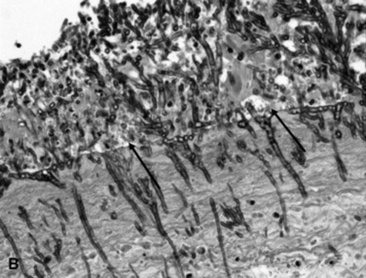

Viral agents are frequently implicated or suspected but rarely identified by the usual serologic, histopathologic, and virus isolation methods. The advent of more sensitive and specific techniques, such as in situ PCR and monoclonal antibody IHC, may partially resolve the current diagnostic challenge. Most recently, a novel gamma-EHV, EHV type 5 (EHV-5), has been found associated with a nodular form of interstitial pneumonia of horses characterized by pulmonary interstitial fibrosis, suggesting that these rather unusual cases may have an underlying infectious cause.420 This disease has been termed equine multinodular pulmonary fibrosis by the authors describing the pathology of the disease. Horses affected generally have a history of fever, cough, and weight loss, accompanied by exercise intolerance and finally respiratory distress. They can be acutely affected or have a more chronic progressive problem. Typical radiographs reveal multiple discreet to coalescing nodular densities overlying a diffuse interstitial pattern (Figs. 31-31 and 31-32). Histologic appearance is diagnostic of this disease (Figs. 31-33 and 31-34). EHV-5 has been identified in both BALF and lung biopsy samples from affected patients by both PCR assay and IHC.

image

Fig. 31-33 Postmortem histopathologic specimen from a horse with severe equine multinodular pulmonary fibrosis. This is the histologic appearance of one of the fibrotic nodules. The alveoli are constricted within dense neoformed fibrotic tissue. Alveoli have an abnormal cuboidal epithelium (type 2 pneumocytes), and the lumen contains macrophages, sloughed epithelial cells, and neutrophils. Denser and diffuse fibrotic areas present.

Courtesy Dr. Fabio Del Piero, University of Pennsylvania, New Bolton Center, Kennett Square, Penn.

Fig. 31-34 Postmortem histopathologic specimen from a horse with severe equine multinodular pulmonary fibrosis. Note abnormal alveolar cuboidal epithelium, and within the lumen neutrophils and intranuclear amphophilic viral inclusion with chromatic margination within a sloughed epithelial cell or perhaps a macrophage.